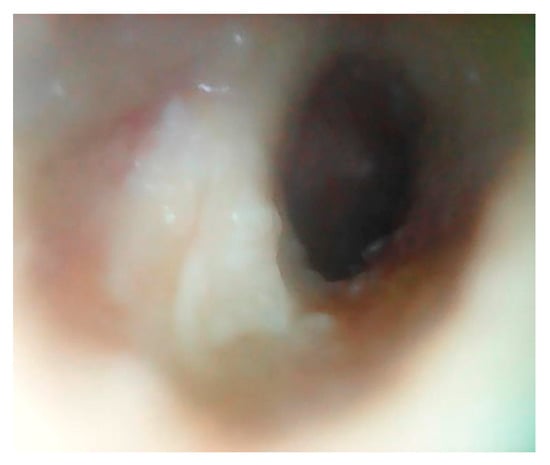

3.1. Patient 1

3.2. Patient 2

3.3. Patient 3